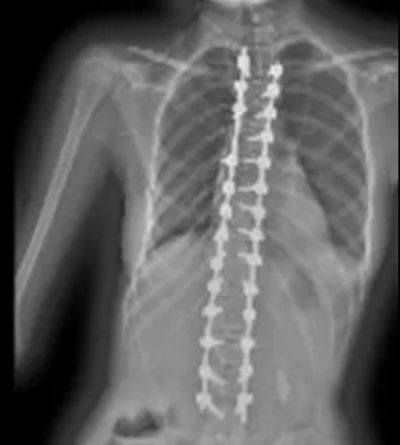

历经6个小时精细操作,手术圆满成功。术后X光显示,小范的脊柱侧弯从58°矫正至8°,矫正率达86%,外观显著改善,身高也从158厘米增至162厘米。

▲ 术后X线